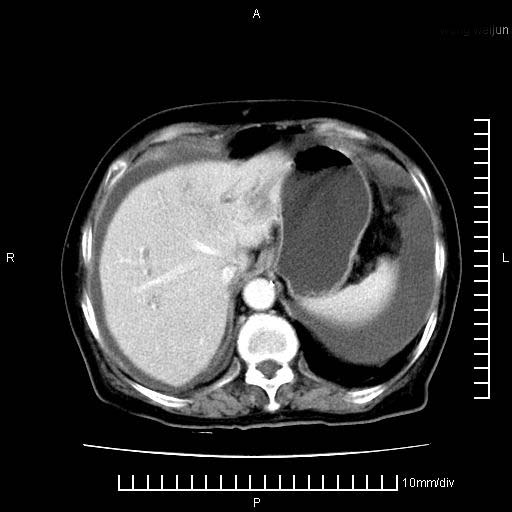

标题: CT28280:腹部增强:女性,80岁

上腹疼痛月余,外院核磁诊断胰腺癌。现临床示右下腹可明显触及包块,可片子上怎么没有看到?

1。胰腺ca伴腹膜腔转移

2。肝左叶低密度灶,考虑转移可能

支持胰腺癌肝内转移,腹水改变。

1、考虑胰腺癌伴腹膜腔转移,胸腹水。

2、肝脏转移可能。

考虑胰腺ca伴腹膜腔转移、肝左叶转移、右肾积水。右胸腔积液。